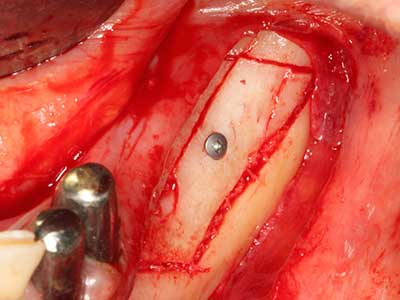

Sollen chirurgische Eingriffe mit unmittelbarer Knochenbeziehung an empfindlichen Strukturen wie Blutgefäßen oder Nerven erfolgen, so bergen rotierende Instrumente ein erhebliches Potential an iatrogener Schädigung. Gerade bei Nervdarstellungen nach iatrogener Schädigung, oder aber im Zuge einer Nervlateralisation für resektive und rekonstruktive Eingriffe oder Implantatinsertionen können piezoelektronische Geräte hilfreich sein Knochendeckel zu präparieren und nervnahe Hartgewebsanteile zu entfernen (Abb. 17-20). Ein leichter Kontakt des Nervstrangs zur Piezospitze bleibt dabei in der Regel folgenlos – allerdings kann eine unvorsichtige Vorgehensweise mit sägeartigen Bewegungen bzw. Ansätzen bei noch vorhandener knöcherner Unterlage durchaus temporäre oder aber auch permanente Nervschädigungen verursachen. Das Risiko einer solchen Schädigung wird jedoch als wesentliche geringer eingeschätzt als unter Anwendung von Säge- oder Fräsinstrumenten (Pereira, Gealh et al. 2014).

Wie sich in der Vergangenheit gezeigt hat stellt prinzipiell jeder knochenchirurgische Eingriff eine mögliche Indikation für die Piezochirurgie dar. So lässt sich die Präparation des mobilen Segmentes bei der Distraktionsosteogenese (Abb. 23-25) und der Sandwichosteotomie mit speziellen Ansätzen bewerkstelligen, ohne die für den Erfolg beider Techniken essenzielle Blutversorgung des krestalen Anteils zu gefährden (Gonzalez-Garcia, Diniz-Freitas et al. 2008).

Für die Entnahme von Implantaten ist die Präparation eines vestibulären Knochendeckels möglich, der nach Entfernung der Implantatschraube refixiert wird und auf diesem Wege die Kontur des Alveolarfortsatzes erhält.

Weitere Einsatzgebiete ergeben sich in der Kieferhöhlenchirurgie: Hier können nach konzentrischer Präparation eines in der Regel trapezförmigen Knochendeckels der fazialen Kieferhöhlenwand Pathologien und Fremdkörper aus der Kieferhöhle entfernt werden. Der Knochendeckel wird nach Abschluss des intra-antralen Operationsanteils reponiert und durch Verkeilen oder adaptierende Nähte gegen Dislokation gesichert.